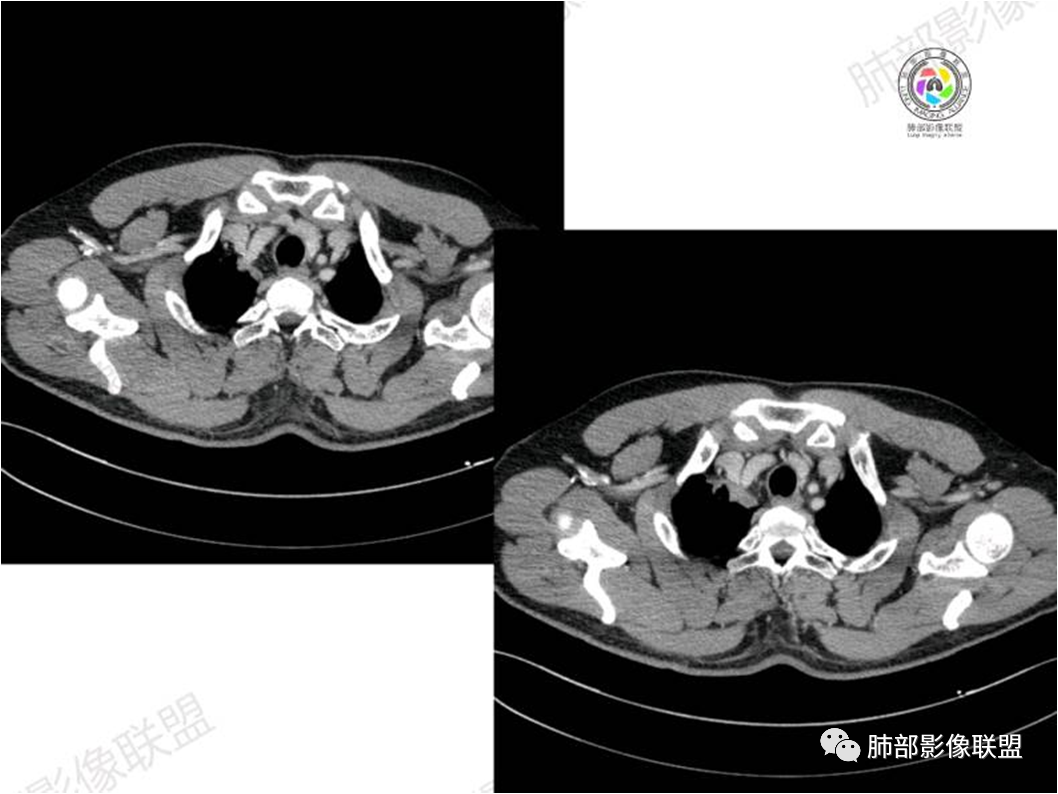

MALT淋巴瘤影像表现为实变、结节及磨玻璃影,其中实变是其特点,胸膜下或支气管血管束节段性分布具有特征性,跨叶征较常见,这可能与肿瘤细胞进入血循环后往往又回到上皮黏膜部位,它们从一处黏膜到另一处黏膜,但不会到外周淋巴组织等有关。国外多名学者的影像-病理研究报道认为其病理学基础是由于肿瘤细胞沿支气管血管束周围间质及胸膜浸润生长,形成小叶间隔增厚、支气管血管束增粗等间质性改变,进一步浸润肺泡壁、充填肺泡腔。

①实变的出现率100%,多表现为两(89%)或单肺多发,密度均匀,与邻近胸壁肌肉的密度大致相等,少见钙化(15%),这与病灶内血管保持 完整,血供丰富,且肿瘤生长缓慢,对缺氧耐受好,不易坏死有关。边缘磨玻璃影或晕征具有特异性,其病理学基础是肿瘤细胞对小叶间隔、肺泡壁的淋巴瘤样浸润;

③扩张的充气支气管为其较特征性的表现,出现率约为89%,支气管管壁无破坏,支气管常扩张并达病灶的边缘,这与炎症性肺癌明显不同,其病理学基础是肿瘤起源于肺间质,肿瘤细胞沿着脏器解剖结构生长,周围增生的结缔组织牵拉导致支气管扩张,因而这类支气管扩张在肿瘤治疗后有时可消失;

④血管造影征是另一 点,强化的肺血管形态及走行正常,无扭曲或增 粗,其病理学基础为肿瘤细胞沿间质增生浸润,不破坏血管或支气管,病灶内肺支架结构完整,本研究发现率为75%;